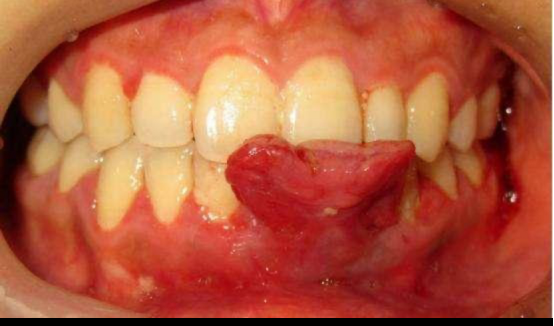

在孕前就患有牙龈炎或牙周炎的女性,怀孕后炎症会更加严重,牙龈会出现增生,肿胀,出血显著,个别的牙龈还会增生至肿瘤状,称为妊娠性牙瘤,极易出血,严重时还会妨碍进食。

图二:妊娠性牙瘤